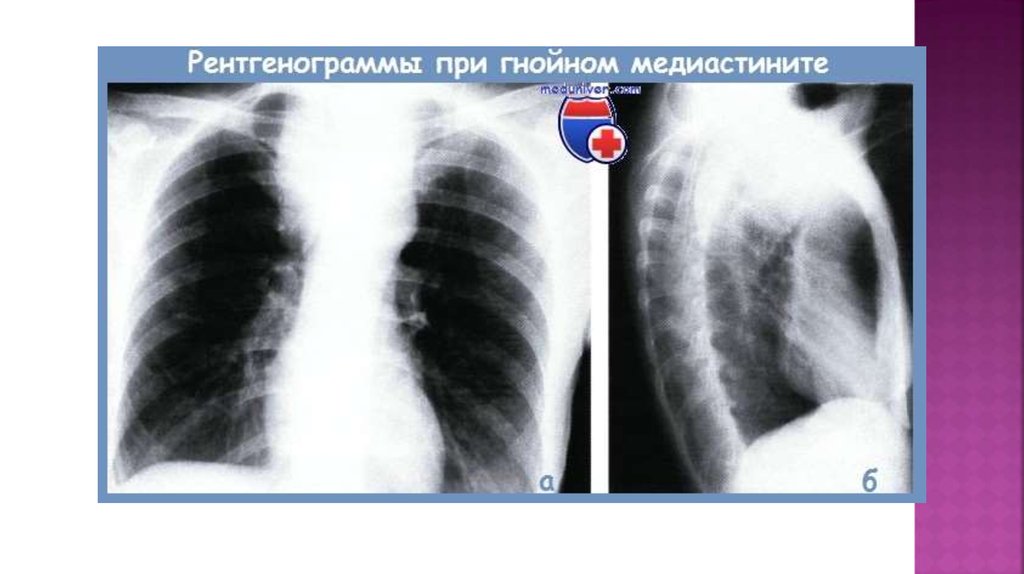

18. Диагностикасы

Инструментальды:

Рентгенография және томография